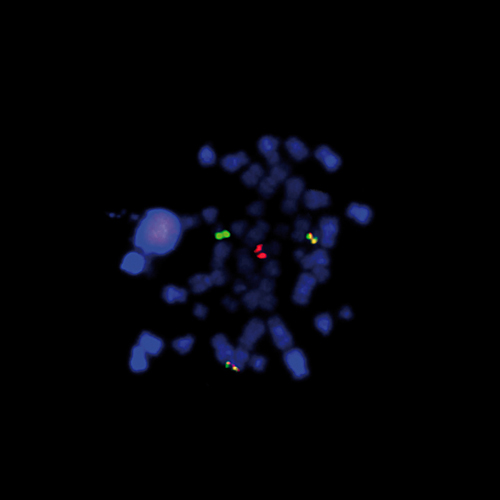

KMT2A / MLLT1 t(11;19) Fusion probe hybridized to patient material showing t(11;19) translocation (2RG1R1G).

One of the relatively frequently observed translocations (around 10 %) in AML and ALL involves the genes KMT2A (previously known as MLL) and MLLT1 (aka ENL) at 11q23 and 19p13. The KMT2A/MLLT1 translocation results in the generation of fusion protein that retains the MLL N-terminus, including both an A-T hook domain and a region similar to mammalian DNA methyltransferase. There are several breakpoints within the MLLT1 gene described, without clear differences in clinicohematologic features. The KMT2A/MLLT1 Fusion probe is optimized to detect translocations involving the KMT2A and MLLT1 gene regions at 11q23 and 19p13 in a dual-color, fusion assay on metaphase/interphase spreads, blood smears and bone marrow cells in a dual-color, fusion assay.